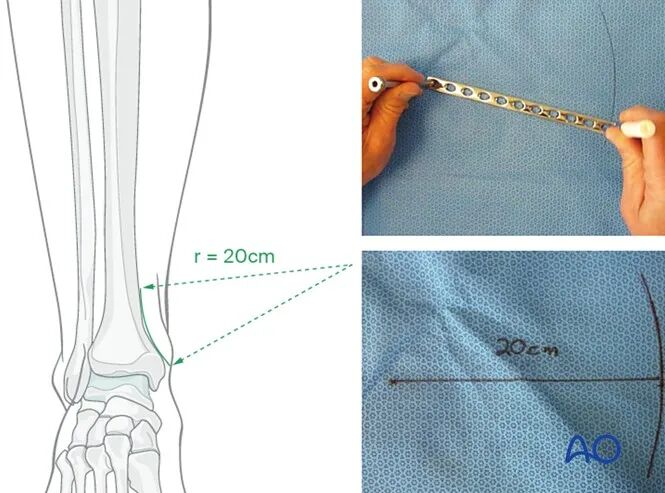

曲率匹配塑形

根据接骨板的置入位置,需对其进行不同程度的弯曲塑形,以贴合完整骨(或复位后骨折端)的表面轮廓。胫骨干内侧大部分区域相对平直,仅需少量弯曲塑形;而胫骨远端内侧表面存在明显凹陷,其曲率半径通常为20 cm,具体形态如图所示。

可在无菌手术单上绘制半径20 cm的弧形,作为该部位接骨板塑形的模板。

接骨板弯曲塑形

●接骨板可单纯使用折弯器进行弯曲塑形,但建议优先采用折弯机,其塑形可控性更强。

●无论采用何种工具,均需分步小幅弯曲,以形成平滑的轮廓;塑形范围仅限接骨板远端10-12 cm区域,最终使接骨板曲率与20 cm半径的弧形模板匹配。